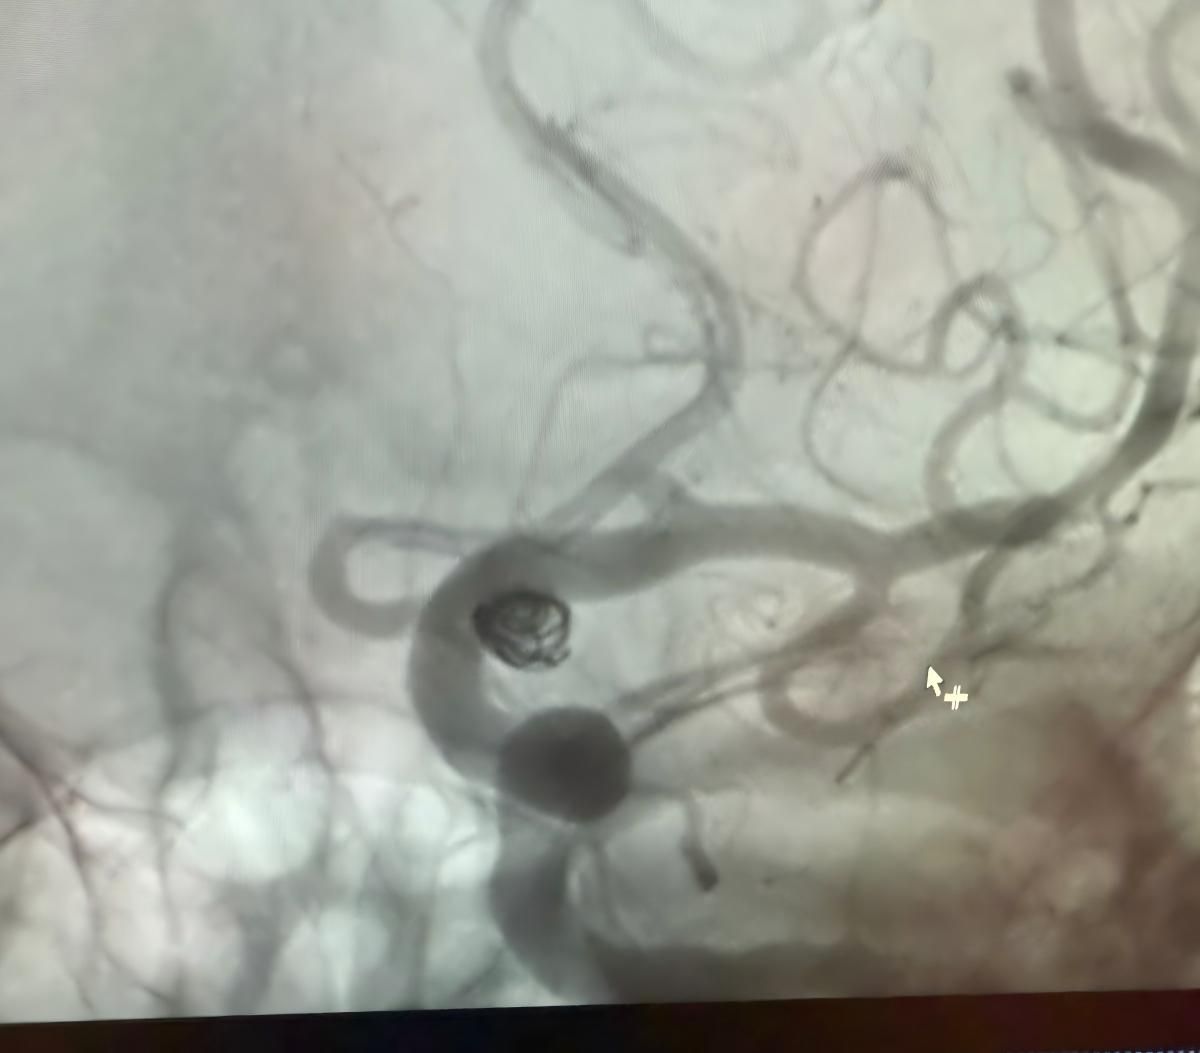

Мы рады поделиться недавней успешной процедурой в Клинике Альма Матер, Медельин, выполненной доктором Хорхе Мутисом.

Лечение использовалось Нува®Отвод потока (TJED-D 5,0-14), перденсатор®3D катушка и Frepass®Микрокатетер (TJMC18 Plus) для аневризмы задней сообщающихся артерий.

Доктор Мутис подчеркнул отличную видимость устройства и отметил, что извлечение было гладким. Он выразил большое удовлетворение в связи с окончательным результатом.